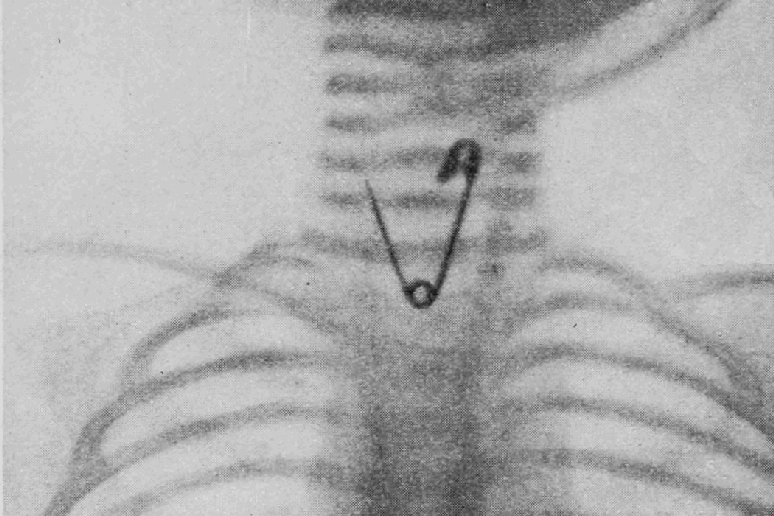

Radiografia feita do primeiro paciente, antes do procedimento cirúrgico. Após nossa análise, dois marcadores, em forma de 0 e 1, foram fixados sobre a pele da criança. O marcador Fonte: acervo pessoal.